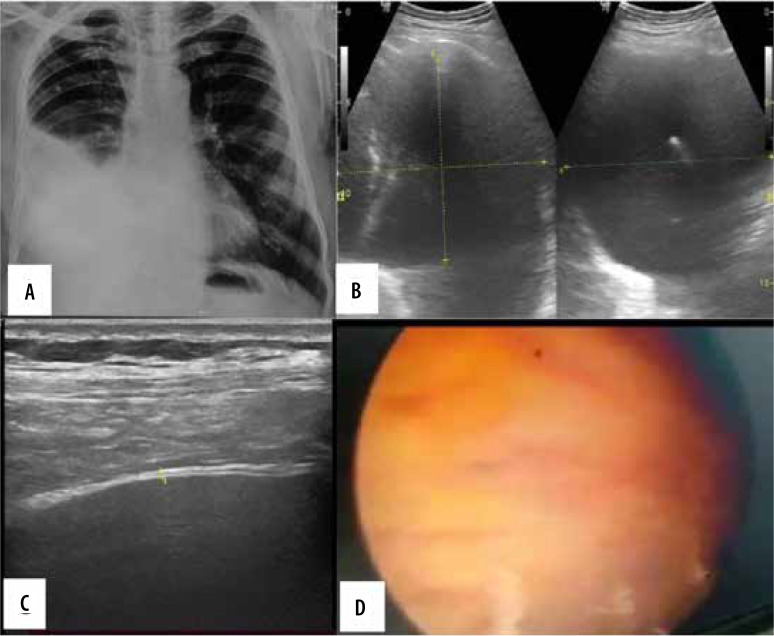

Purpose: The purpose of this study was to evaluate the use of the transthoracic ultrasonography (US) for pleural adhesions and pleural thickening and to quantify pleural effusion by standardised sonographic techniques and its comparison with thoracoscopic findings. An assessment of the association between pleural thickness and pleural nodularity with histopathological examination findings was also attempted.

Material and methods: Thirty-one patients with suspected chest pathologies were initially assessed by transthoracic US followed by videothoracospy. Findings observed were noted and appropriately analysed statistically.

Results: Transthoracic US is 100% sensitive and specific for detecting pleural septations in the presence of pleural effusion with 100% accuracy. Gliding sign is a highly sensitive and specific sign to detect the pleural septations in absence of pleural effusion. There was no significant association of thickness of pleural septation with the pleural malignancy.

Conclusions: Transthoracic US plays an important role in the quantification of pleural effusion, assessment of the pleura and pleural space for pleural adhesion, pleural thickening, and guiding trocar insertion.